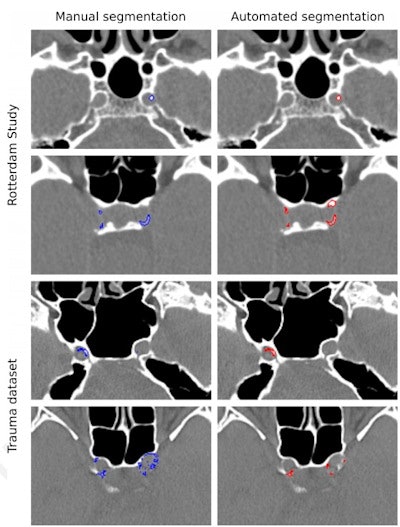

Patients underwent noncontrast CT exams between 2003 and 2006 and were monitored for stroke until January of 2016. For this study, two radiologist readers manually delineated the condition on the CT scans and the deep-learning model was trained to segment intracranial carotid artery calcification and quantify its volume. The model's performance was assessed by comparing the radiologist readers' manual and the model's automated segmentations with those produced by an independent observer, the group wrote.

For identifying ICAC, the deep-learning algorithm showed a sensitivity of 83.8% and a positive predictive value of 88%. Correlation between manually performed and automated ICAC volume measures was 0.98. The researchers also found a strong association of ICAC volume with stroke for both automated and manually measured volumes, with hazard ratios of 1.38 and 1.48, respectively.